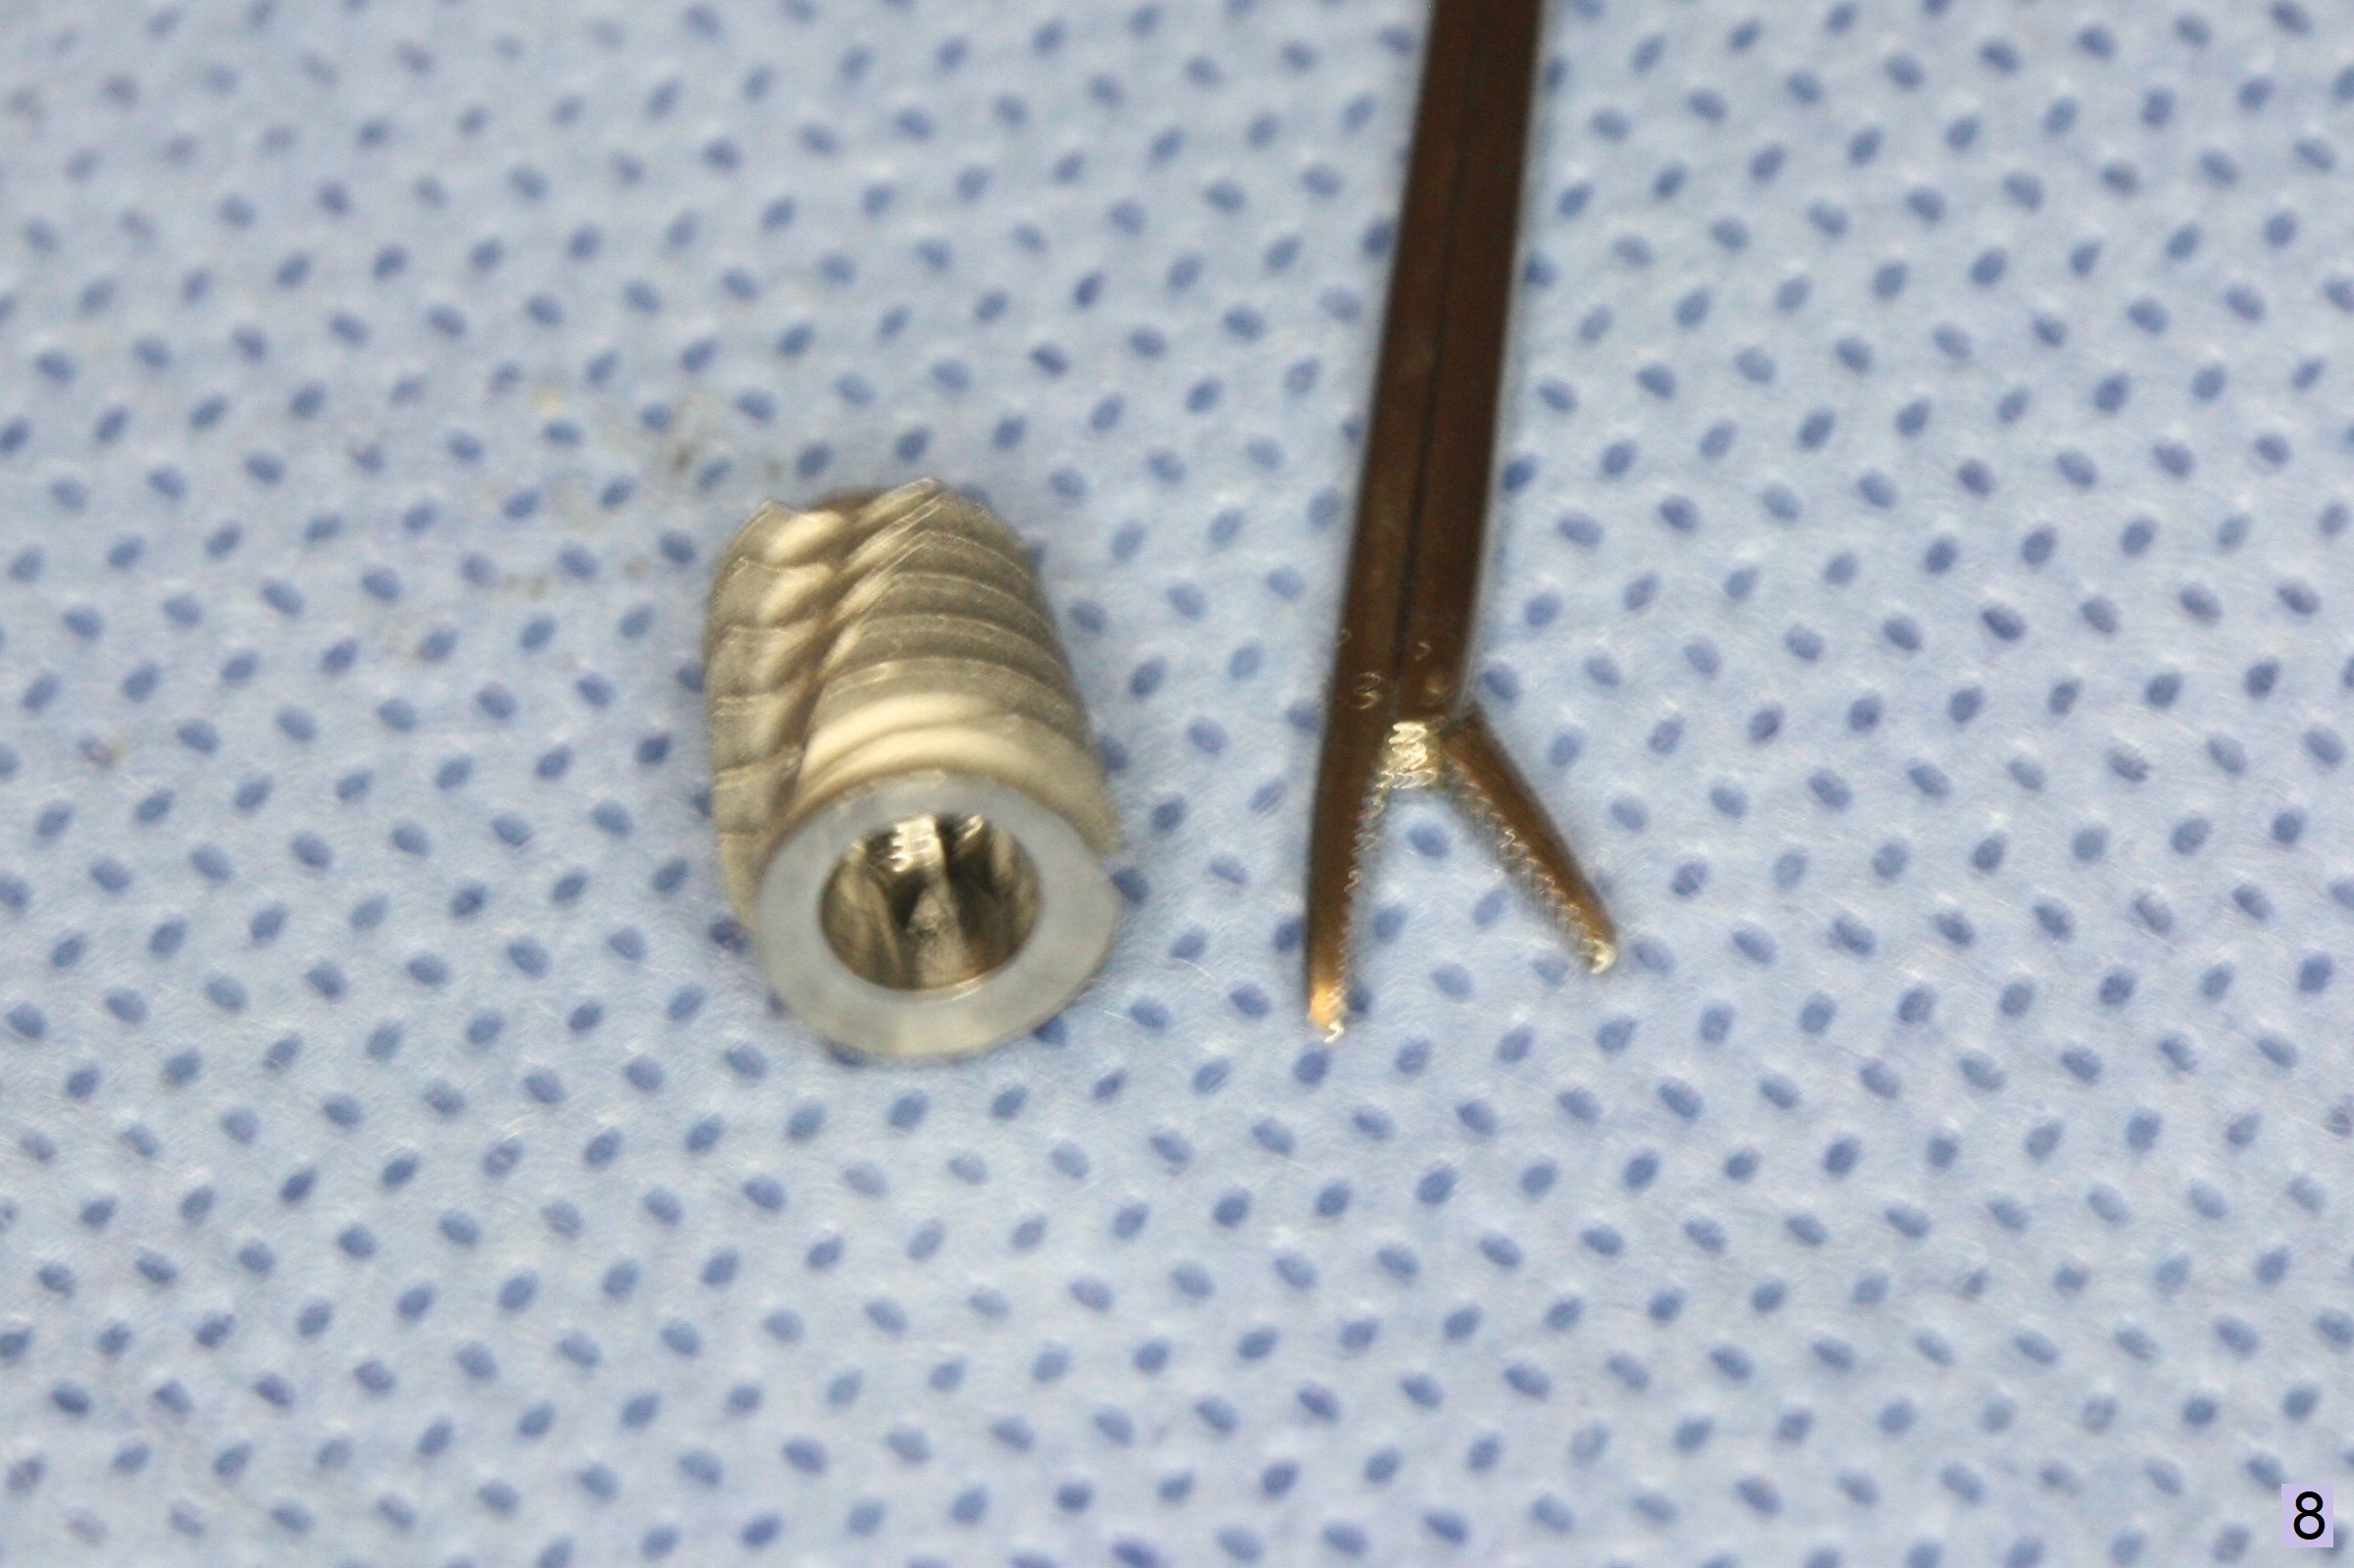

When the displaced tooth #14 (Fig.1) with palatal gingival recession (Fig.2) is extracted, the buccal plate is low, while the palatal one is lost.  Osteotomy is initiated in the bottom of the large socket with Marking Drill.  The bone turns bluish, suggesting thin bone (in fact less than 1 mm as well as low density).  Magic Sinus Lifter (Fig.3 *, Fig.4 blue area) is used for sinus lift (Fig.4 (red curved line: lifted sinus membrane; grey area: a portion of the lifted sinus floor), followed by insertion of a piece of PRF plug and Vanilla bone graft for sinus lift.  The osteotomy is enlarged lightly with 4.8 mm Magic Drill (compare black strips between Fig.4,5).  A 5x9 mm dummy implant (Fig.5 green) is dislodged into the sinus.  The lifted sinus membrane holds the implant in place.  The black thin strip in Fig.5 and black circle in Fig.6a (occlusal view) represents the osteotomy.  After increase in the osteotomy with Lindamann bur (Fig.6b red circle), the implant (Fig.6c green) is retrieved with endodontic forceps (Fig.6c two blue dots (beaks of the forceps); Fig.7,8).  With the enlarged osteotomy (Fig.6d), a 6x9 mm dummy implant is placed deep (Fig.9).  The definitive implant is 6.5x11 mm with insertion torque ~ 15 Ncm (Fig.10).  With placement of a healing screw and further placement of allograft (Fig.11 *), the socket is closed with PRF membrane and collagen plug (Fig.12).